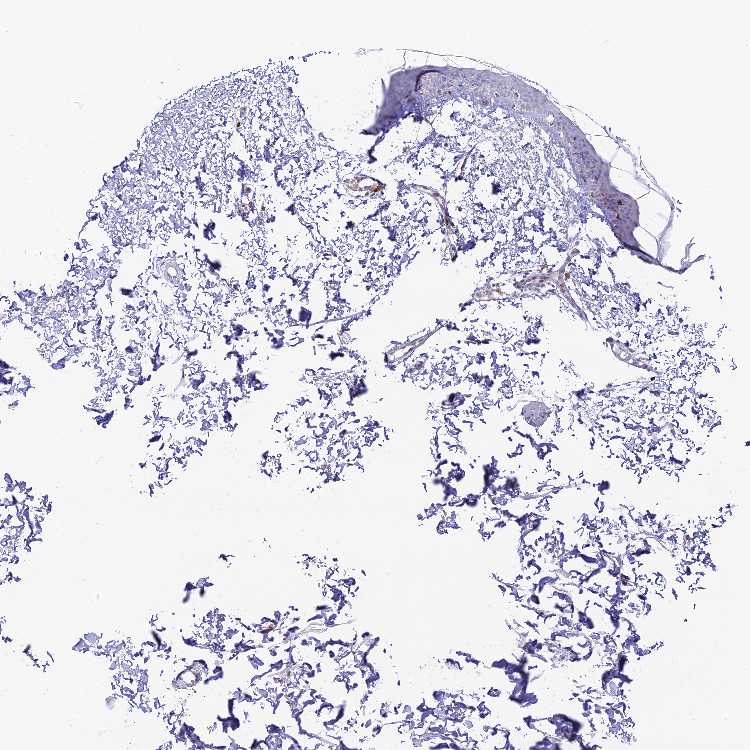

SKIN 2 - Antibody stainingi

Antibody staining in the annotated cell types in the current human tissue is reported as not detected, low, medium, or high, based on conventional immunohistochemistry profiling in selected tissues. This score is based on the combination of the staining intensity and fraction of stained cells.

Each image is clickable and will lead to virtual microscopy that enables deeper exploration of all samples and also displays staining intensity scores, fraction scores and subcellular localization as well as patient and tissue information for each sample.

Antibody HPA042981

Epidermal cells Not detected